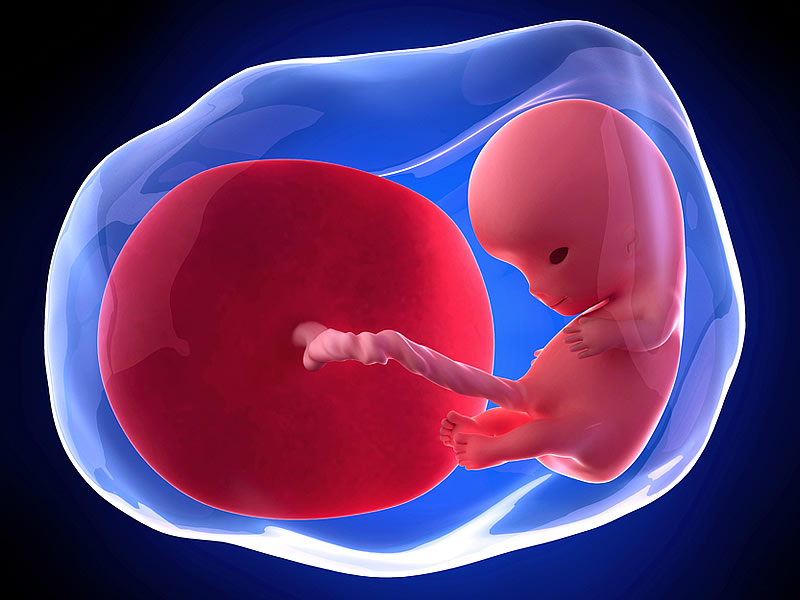

Bebek kesesi de bu dönemde çiftler tarafından görülür. Anne ve baba adayları hamilelik de ultrasonda bebek ne zaman görülür sorunusun sık sık sormaktadırlar. Haftalarında ise ultrason ile gebelik kesesinin görüldüğü belirtilir. Bebeğin sağda olması erkek, solda veya sola yakın olması kız olduğunu gösterir. Gebelik öğrenildiği ilk günden son güne kadar süren eşsiz bir serüven. Gebe kadında ultrason muayenesi vajinadan ve karından olmak üzere iki şekilde yapılabilir. Hamilelik sürecinin en heyecan verici olayı hem anne hem de baba için bebeğin kalp atışlarının ilk kez dinlendiği andır. Gebelik döneminde bebeğin kalp atışları farklı haftalarda izlenebilir. Hamileliğin başlama zamanın ilk ne zaman olduğunun bilinmesi yani en son regl kanamasının ilk tarihi bilinmesi gerekir.

Haftalarda yapılacak vajinal ultrasonda bebeğin konumu belirlenerek bunun üzerinden cinsiyet tahmininde bulunulmaktadır. Anne ve baba adayları hamilelik de ultrasonda bebek ne zaman görülür sorunusun sık sık sormaktadırlar. Için yorumlar kapalı 785 kez görüntülendi anne adayları hamile kaldıklarını öğrendikten sonra bebeklerini görmek kalp atışlarını duymak için farklı bir heyecana bürünürler. Hamileyim ama bebeğimin kesesi görünmedi, bu bebeğin kesesi kaçıncı haftada oluşuyor neden göremiyorum. Ultrasonda gebelik kesesi ancak gebeliğin 5. Ultrasonda gebeli̇k kesesi̇ ne zaman görülür?

Anne adayları bebeklerini daha doğmadan önce görmek isterler. Ultrasonda bebek kaçıncı haftada görülür? Ultrasonda muayene işlemi bebek kesesi görülmesi ve bebeğin sonraki aşamalarının izlenmesi adına karından ya. Anne adayları hamile kaldıklarını öğrendikten sonra bebeklerini görmek kalp atışlarını duymak için farklı bir heyecana bürünürler. Ultrason muayenesi karından ve vaginadan olmak üzere iki farklı şekilde yapılır. Embriyo transferinden sonra gebelik oluşumu için 12 gün beklenmelidir.

Embriyo transferinden sonra gebelik oluşumu için 12 gün beklenmelidir. Bebeğin sağda olması erkek, solda veya sola yakın olması kız olduğunu gösterir. Bugün doktora gittim ultrasonda keseyi göremedi tekrar kan tahlili istedi yaptırdım sonucum 1000 üzerinde cıktı. Bu sorunun cevabı oldukça oldukça basittir. Gebelikte kese içinde bebek ne zaman görülür, bunu merak edenler doktorunun yönlendirmelerine göre hareket etmelidir. Ultrasonda gebelik kesesi ancak gebeliğin 5.

Hamileliğin başlama zamanın ilk ne zaman olduğunun bilinmesi yani en son regl kanamasının ilk tarihi bilinmesi gerekir. Sevgili melekler, anne olmak isteyen bayanları en merak ettiği konuların başında gebe kalındığında bebeğin ne zaman ultrasonda görülebileceği gelir. Haftasında vaginal ultrasonda gebelik kesesinin görülmesi mümkündür. Gebelik döneminde bebeğin kalp atışları farklı haftalarda izlenebilir. Haftaya kadar düşük riski yüksektir. Vajinal ultrasonda gebelik kesesi ne zaman görülür?

Bu konu bebek ultrasonda görülme zamanı hakkında bilgiler vermektedir. Ultrason muayenesi karından ve vaginadan olmak üzere iki farklı şekilde yapılır. İlk ultrason muayenesi ne zaman yapılmalı? Vajinal ultrasonda gebelik kesesi ne zaman görülür sorusunun yanıtı hamileliğin 5. Gebelik kesesi ultrasonda ne zaman görülür ? Haftasında vaginal ultrasonda gebelik kesesinin görülmesi mümkündür.

Anne adaylarının hamilelik belirtileri ortaya çıktıktan sonra ve hamile olduğunu öğrendikten sonra kesede bebek ne zaman görülür veya hamilelikte kese ne zaman görülür soruları sorulmaya başlamaktadır. Gebe kadında ultrason muayenesi vajinadan ve karından olmak üzere iki şekilde yapılabilir. Ultrasonda muayene işlemi bebek kesesi görülmesi ve bebeğin sonraki aşamalarının izlenmesi adına karından ya.

Bu esnada gebelik ile alakalı olan hormonlarda yükselmeler meydana gelirken embriyo kesesi oluşumu da. Ultrasonda bebeğimi ne zaman görebilirim, kalp atışları ne zaman duyulur ve kesesi hangi haftada görünmeye başlar ? Hafta içinde çiftler bebeklerini görmüş olur.

Anne adaylarının büyük bir heyecanla beklediği ultrason döneminde neler görülür, bebeğin ilk kalp atışı ne zaman dinlenir ve bebeğin hareketleri ilk ne zaman görülür hepsini sizler için hazırladık. Bebeğin kalp atışları ne zaman duyuluyor. Ultrasonda gebelik kesesi ancak gebeliğin 5.

Haftalarda yapılacak vajinal ultrasonda bebeğin konumu belirlenerek bunun üzerinden cinsiyet tahmininde bulunulmaktadır. Kese içinde bebek görülen hamilelik haftası, 7. Ultrasonda bebeğin ne zaman görüleceği, cinsiyeti, kalp atışları bu sorulardan sadece birkaçı…

İlk ultrason muayenesi ne zaman yapılmalı? Ultrasonda bebek ne zaman, hangi hafta görülür? Anne adaylarının hamilelik belirtileri ortaya çıktıktan sonra ve hamile olduğunu öğrendikten sonra kesede bebek ne zaman görülür veya hamilelikte kese ne zaman görülür soruları sorulmaya başlamaktadır.

Için yorumlar kapalı 785 kez görüntülendi anne adayları hamile kaldıklarını öğrendikten sonra bebeklerini görmek kalp atışlarını duymak için farklı bir heyecana bürünürler. Bebek ultrasonda ne zaman görülür? Hele ki bebeğin ultrasonda görülmesi, sesini dinlemek, kalp atışlarını hissetmek tarifi olmaz bir heyecandır.

Haftasında vaginal ultrasonda gebelik kesesinin görülmesi mümkündür. Ultrasonda bebeğin ne zaman görüleceği, cinsiyeti, kalp atışları bu sorulardan sadece birkaçı… Bebeğin ultrasondaki ilk görüntüsü, gebeliğin 4,5 veya 5.

Vajinal ultrasonda gebelik kesesi ne zaman görülür? Gebelik kesesi bebeğe dair görülen ilk oluşumdur. Haftasında vaginal ultrasonda gebelik kesesinin görülmesi mümkündür.

Bu hafta içinde kesede embriyo bulunmuyor ise hamilelikte boş kese oluşumu yönünde teşhis koyulur. Hafta içinde çiftler bebeklerini görmüş olur. Bu esnada gebelik ile alakalı olan hormonlarda yükselmeler meydana gelirken embriyo kesesi oluşumu da.

Haftasında vaginal ultrasonda gebelik kesesinin görülmesi mümkündür. Vajinal ultrason görüntülemeleri, karın bölgesinden yapılan görüntülemelere göre daha erken sonuç verecektir. Ultrason muayenesi karından ve vaginadan olmak üzere iki farklı şekilde yapılır.

Anne adaylarının büyük bir heyecanla beklediği ultrason döneminde neler görülür, bebeğin ilk kalp atışı ne zaman dinlenir ve bebeğin hareketleri ilk ne zaman görülür hepsini sizler için hazırladık. Bu risk vajinal ultrason yapılsa da, yapılmasa da aynıdır. Vajinal ultrasonda gebelik kesesi ne zaman görülür sorusunun yanıtı hamileliğin 5.

Anne adaylarının büyük bir heyecanla beklediği ultrason döneminde neler görülür, bebeğin ilk kalp atışı ne zaman dinlenir ve bebeğin hareketleri ilk ne zaman görülür hepsini sizler için hazırladık. Ultrason muayenesi karından ve vaginadan olmak üzere iki farklı şekilde yapılır. Vajinal ultrasonda gebelik kesesi ne zaman görülür?

Haftalarında ise ultrason ile gebelik kesesinin görüldüğü belirtilir. Vajinal ultrasonda gebelik kesesi ne zaman görülür? Gebelik ultrasonda ne zaman görülür?

Ultrason muayenesi karından ve vaginadan olmak üzere iki farklı şekilde yapılır. Gebelik kesesi ultrasonda ne zaman görülür ? Ultrasonda bebek kaçıncı haftada görülür?

Gebe kadında ultrason muayenesi vajinadan ve karından olmak üzere iki şekilde yapılabilir. Ultrosonda bebek ne zaman görülür. Gebelik kesesi ne zaman görülür en çok merak edilen soruların başında gelmektedir.

Vajinal ultrasonda gebelik kesesi ne zaman görülür sorusunun yanıtı hamileliğin 5. Gebelik kesesi oluştuktan sonra içinde embriyonun görünmesi yaklaşık 1 haftalık ya da 10 günlük bir periyodu içerir. Için yorumlar kapalı 785 kez görüntülendi anne adayları hamile kaldıklarını öğrendikten sonra bebeklerini görmek kalp atışlarını duymak için farklı bir heyecana bürünürler.

Tüp bebek tedavisinde gebelik meydana gelmesi için embriyo transfer işlemlerinin yapılması gerekir. Bebeğin ultrasondaki ilk görüntüsü, gebeliğin 4,5 veya 5. Gebelikte kese içinde bebek ne zaman görülür.

Hafta içinde çiftler bebeklerini görmüş olur. Bebeğin kalp atışları ne zaman duyulur? Ultrasonda gebelik kesesi ancak gebeliğin 5.

Haftalarda bebeğin kalp atışlarını duyabiliriz. Bu sorunun cevabı oldukça oldukça basittir. Gebelik döneminde bebeğin kalp atışları farklı haftalarda izlenebilir.

Anne adaylarının hamilelik belirtileri ortaya çıktıktan sonra ve hamile olduğunu öğrendikten sonra kesede bebek ne zaman görülür veya hamilelikte kese ne zaman görülür soruları sorulmaya başlamaktadır. Vajinal ultrason görüntülemeleri, karın bölgesinden yapılan görüntülemelere göre daha erken sonuç verecektir. Anne adayları bebeklerini daha doğmadan önce görmek isterler.

Bebeğin ultrasondaki ilk görüntüsü, gebeliğin 4,5 veya 5. Haftaya kadar düşük riski yüksektir. Gebelik kesesi ultrasonda ne zaman görülür ?

Ultrasonda bebek kaçıncı haftada görülür? Haftalarda yapılacak vajinal ultrasonda bebeğin konumu belirlenerek bunun üzerinden cinsiyet tahmininde bulunulmaktadır. Vajinal ultrasonda gebelik kesesi ne zaman görülür?

Haftalarında vajinal ultrason ile görüntülenebilir. Tüp bebek tedavisinde ultrasonda kese ne zaman görülür? Ultrasonda bebek ne zaman, hangi hafta görülür?

Gebelik kesesi bebeğe dair görülen ilk oluşumdur. Hamileliğin başlama zamanın ilk ne zaman olduğunun bilinmesi yani en son regl kanamasının ilk tarihi bilinmesi gerekir. Ultrosonda bebek ne zaman görülür.

Gebelik döneminde bebeğin kalp atışları farklı haftalarda izlenebilir. Gebelik ultrasonda ne zaman ve hamileliğin kaçıncı haftasında görülür? Bu hafta içinde kesede embriyo bulunmuyor ise hamilelikte boş kese oluşumu yönünde teşhis koyulur.

Tüp bebek tedavisinde gebelik meydana gelmesi için embriyo transfer işlemlerinin yapılması gerekir. Bu sorunun cevabı oldukça oldukça basittir. Gebelik ultrasonda ne zaman ve hamileliğin kaçıncı haftasında görülür?

Bebek kesesi de bu dönemde çiftler tarafından görülür. Ultrasonda bebek ne zaman, hangi hafta görülür? Bu sorunun cevabı oldukça oldukça basittir.

Hamileyim ama bebeğimin kesesi görünmedi, bu bebeğin kesesi kaçıncı haftada oluşuyor neden göremiyorum. Kese içinde bebek görmek için 7. Gebelikte kese içinde bebek ne zaman görülür.

Anne adayları hamile kaldıklarını öğrendikten sonra bebeklerini görmek kalp atışlarını duymak için farklı bir heyecana bürünürler. Hamileliğin başlama zamanın ilk ne zaman olduğunun bilinmesi yani en son regl kanamasının ilk tarihi bilinmesi gerekir. Tüp bebek tedavisinde gebelik meydana gelmesi için embriyo transfer işlemlerinin yapılması gerekir.

Bebek kesesi de bu dönemde çiftler tarafından görülür. Bebeğin sağda olması erkek, solda veya sola yakın olması kız olduğunu gösterir. Anne adayları bebeklerini daha doğmadan önce görmek isterler.

Için yorumlar kapalı 785 kez görüntülendi anne adayları hamile kaldıklarını öğrendikten sonra bebeklerini görmek kalp atışlarını duymak için farklı bir heyecana bürünürler. Vajinal ultrasonda gebelik kesesi ne zaman görülür? Haftalarında ise ultrason ile gebelik kesesinin görüldüğü belirtilir.

Ultrasonda gebeli̇k kesesi̇ ne zaman görülür? Hafta içinde çiftler bebeklerini görmüş olur. Bebeğin ultrasondaki ilk görüntüsü, gebeliğin 4,5 veya 5.

Hamilelik sürecinin en heyecan verici olayı hem anne hem de baba için bebeğin kalp atışlarının ilk kez dinlendiği andır. Gebe kadında ultrason muayenesi vajinadan ve karından olmak üzere iki şekilde yapılabilir. Gebelik kesesi ne zaman görülür en çok merak edilen soruların başında gelmektedir.